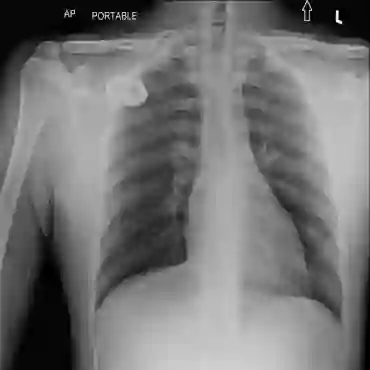

The availability of large public datasets and the increased amount of computing power have shifted the interest of the medical community to high-performance algorithms. However, little attention is paid to the quality of the data and their annotations. High performance on benchmark datasets may be reported without considering possible shortcuts or artifacts in the data, besides, models are not tested on subpopulation groups. With this work, we aim to raise awareness about shortcuts problems. We validate previous findings, and present a case study on chest X-rays using two publicly available datasets. We share annotations for a subset of pneumothorax images with drains. We conclude with general recommendations for medical image classification.